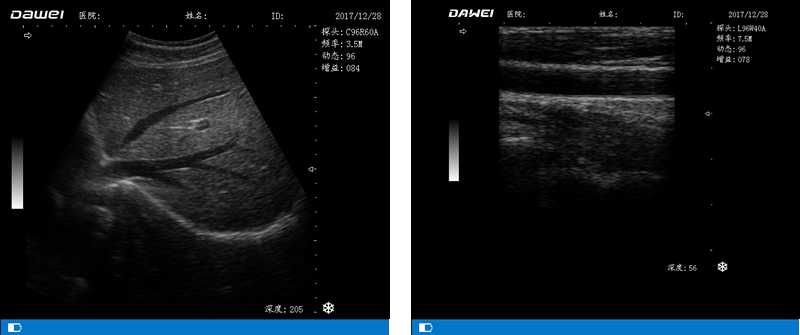

DW-500

筆記本全數(shù)字超聲診斷儀

高陣元 高清晰度 多功能

多倍率顯示 病變診斷更準(zhǔn)確